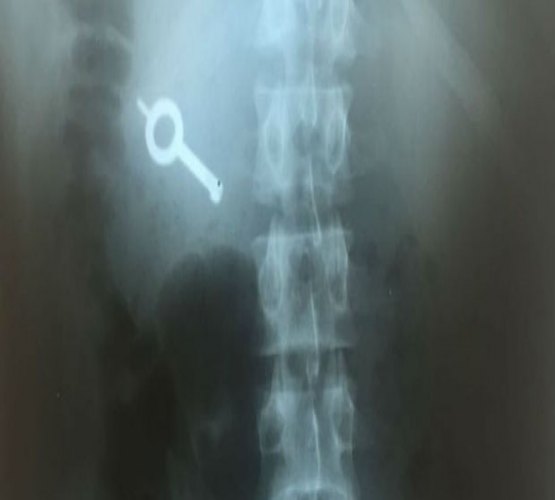

No momento, os homens seguraram o funcionário e pegaram o molho de chaves. Os detentos quebraram câmeras de segurança e tomaram o corredor.